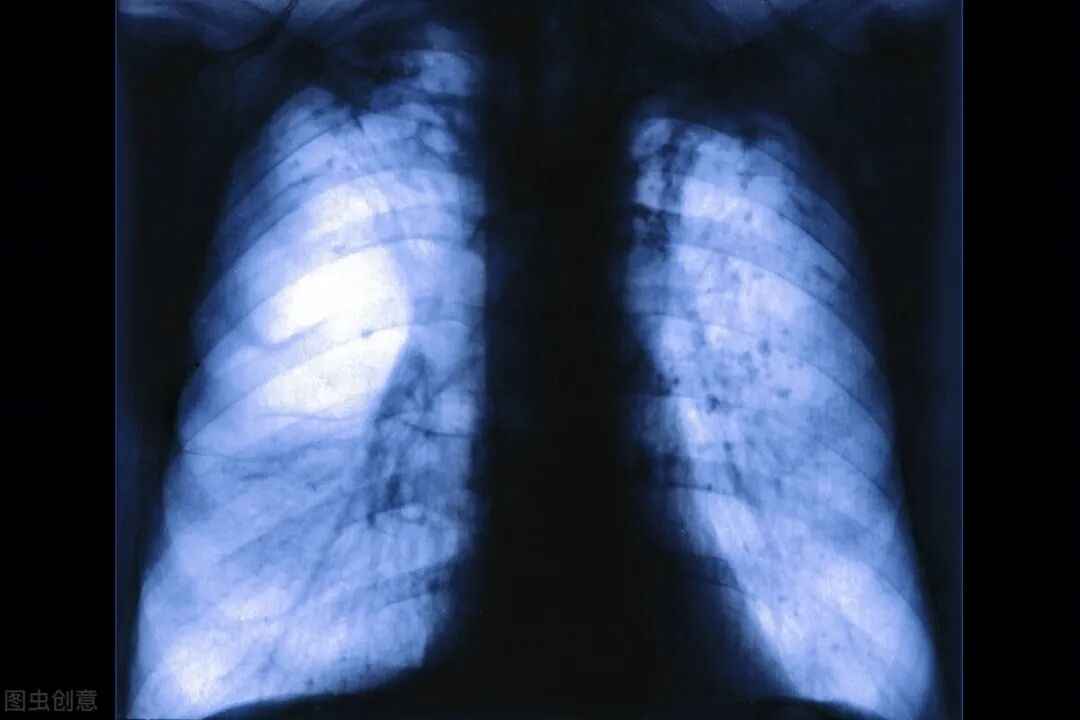

所以说,肺气肿不是一个小问题,必须要重视。一旦发现肺气肿,必须去医院呼吸内科做肺功能检查,看看有没有慢阻肺了,如果有了,一定要及早积极治疗,首选吸入长效支气管扩张剂(塞托溴铵等),还有,必须要戒烟。